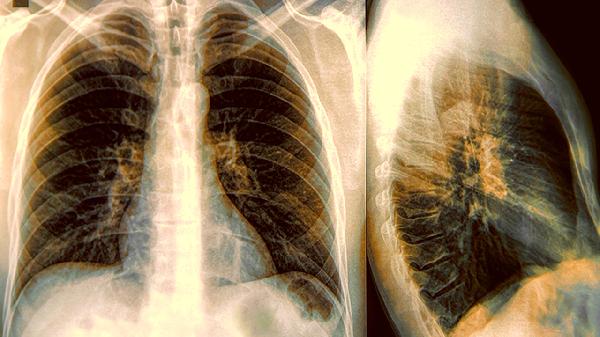

肺结节钙化通常是指肺部结节内部出现钙盐沉积的影像学表现,可能与陈旧性炎症、结核愈合、良性肿瘤等因素有关。肺结节钙化的原因主要有陈旧性感染、结核愈合、错构瘤、肺内淋巴结钙化、转移性钙化等。

肺部既往细菌或真菌感染愈合后,局部可能形成钙化灶。这类钙化结节边缘清晰,直径多在10毫米以内,胸部CT可见高密度钙化影。一般无须特殊治疗,建议定期随访观察,避免吸烟等肺部刺激因素。

肺结核病灶愈合过程中常出现钙盐沉积,形成特征性层状或斑点状钙化。可能伴随纤维条索影,部分患者有结核病史。可遵医嘱使用异烟肼片、利福平胶囊等药物预防复发,同时需加强营养支持。

肺错构瘤是常见的良性肿瘤,约30%病例可见爆米花样钙化。CT显示边界清楚的圆形结节,可能含脂肪密度影。若结节增大或出现症状,可考虑胸腔镜手术切除,平时应避免剧烈运动撞击胸部。